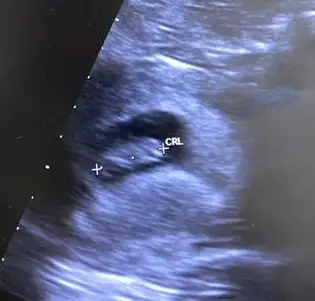

Erkek bebek gibi canım 2. Resimde. İlk foto vajinamı karından mı daha detaylı tek atarmısınikiside karından bakıldı. ilk ultrason 8. hafta ikincisi se 12. haftaya ait. Çok teşekkür ederim şimdiden

Eki Görüntüle 3270094 Eki Görüntüle 3270095

Erkek görünüyorYaa benim içinde hesaplama yapabilir misiniz acabaa?